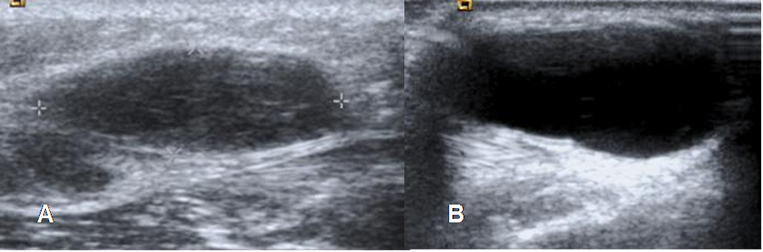

Fig 5. Diferenciación lesiones en ecografía.

A y B: Ecografía. Lesión sólida que corresponde a lipoma en A y lesión quística, que produce reforzamiento posterior en B, por quiste de baker.